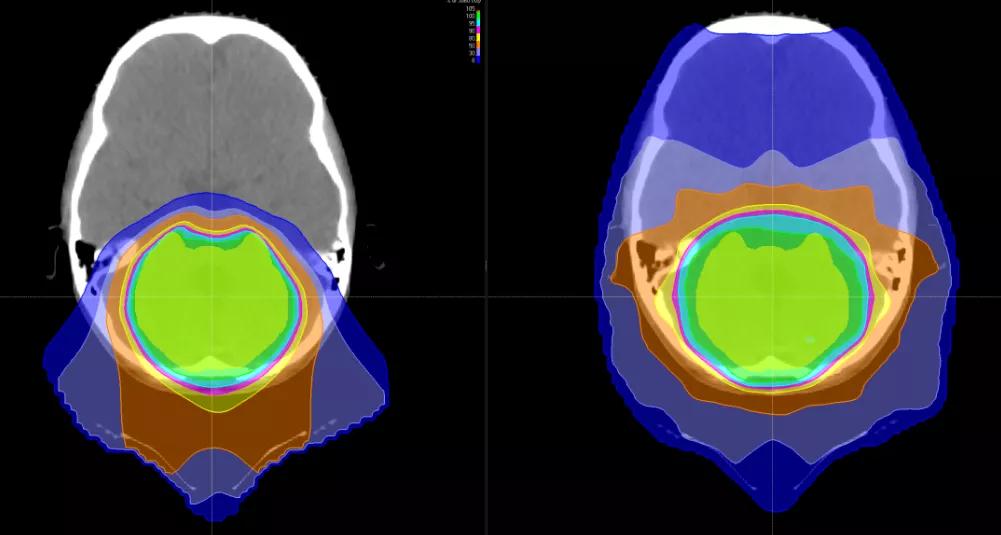

但是明确癫痫是哪个具体部位放电引起的,最常规和直接可靠的就是脑电,通过电生理的脑电监测,可以观察到异常放电的具体情况。现在随着影像学的发展,可以通过磁共振检查,目的是检查脑部是否存在解剖或发育上的异常,有时这也成为癫痫的病理基础。

癫痫的发生与脑肿瘤的类型和发生部位有关。一般来说,生长在大脑前半部、靠近大脑皮层的肿瘤易发生癫痫,即生长缓慢,呈膨胀性生长的肿瘤则癫痫发生率较高。以上类型的肿瘤大多是良性或恶性度不高的,发生部位也容易手术切除,如能早期诊断并手术,能取得满意效果。